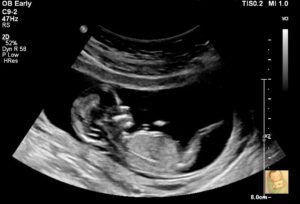

At the twenty-week scan, the sonographer mentioned that the placenta was low-lying and blocking the cervix. Since this was my first pregnancy, he said the placenta usually moves out of the way.

I was wheeled into the birthing ward, and the doctors checked to see if my cervix was dilating. Thankfully, it wasn’t. They looked for your heartbeat while I waited with bated breath—and there it was, thumping steadily and loudly without a care in the world.

There were many blessings that I would not have experienced if I had not been hospitalised. Every morning, a midwife would wheel the cardiotocograph (CTG) machine into my room to monitor your heartbeat. It became a daily communion between you and me. Every day, I studied the rhythm of your life inside my womb, like the way your heart quickens when you kick. I learned to locate your bum, back and head; when the midwives came in for a check, I could point where your chest lay.